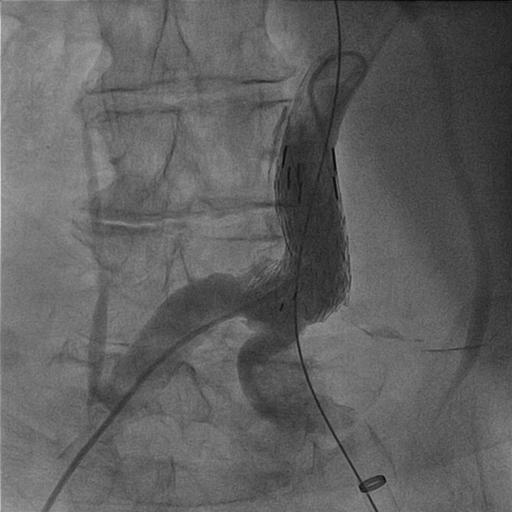

Endovascular aneurysm repair (EVAR) is an adequate means for treating infrarenal abdominal aortic aneurysms (AAA). However, secondary interventions are required in approximately 15% to 20% of patients. The aim of this paper was to report our knowledge with stent grafts in secondary interventions after EVAR in a 73-year-old patient. One of the exceptional complications of EVAR are endoleaks which may lead to expansion of aneurysm and rupture if not repaired.